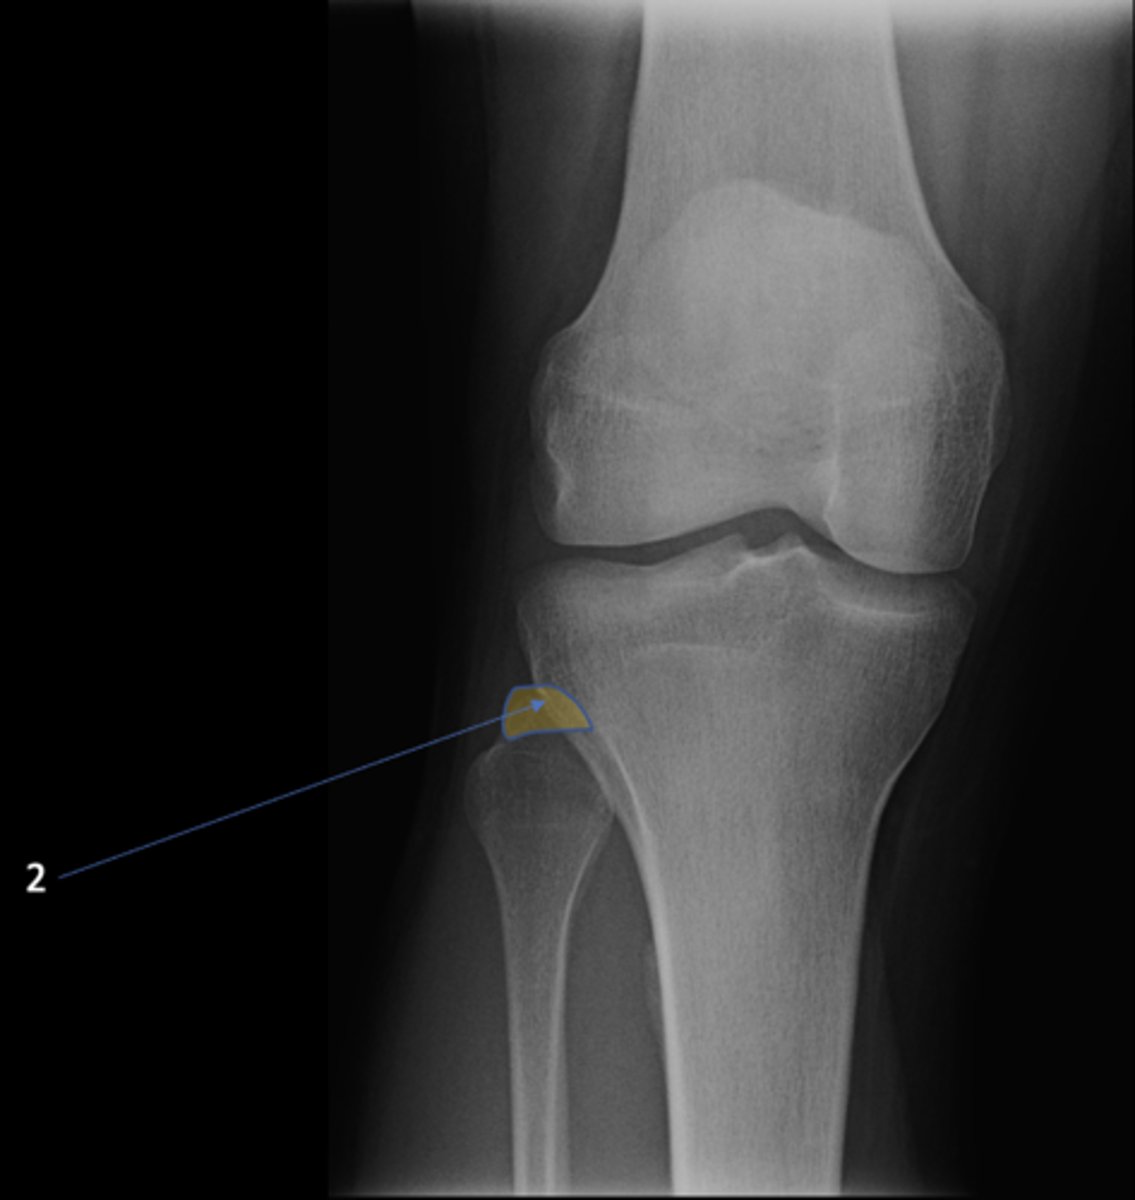

AP knee

View?

<p>View?</p>

50

New cards

Apex of fibular head

ID 2

<p>ID 2</p>